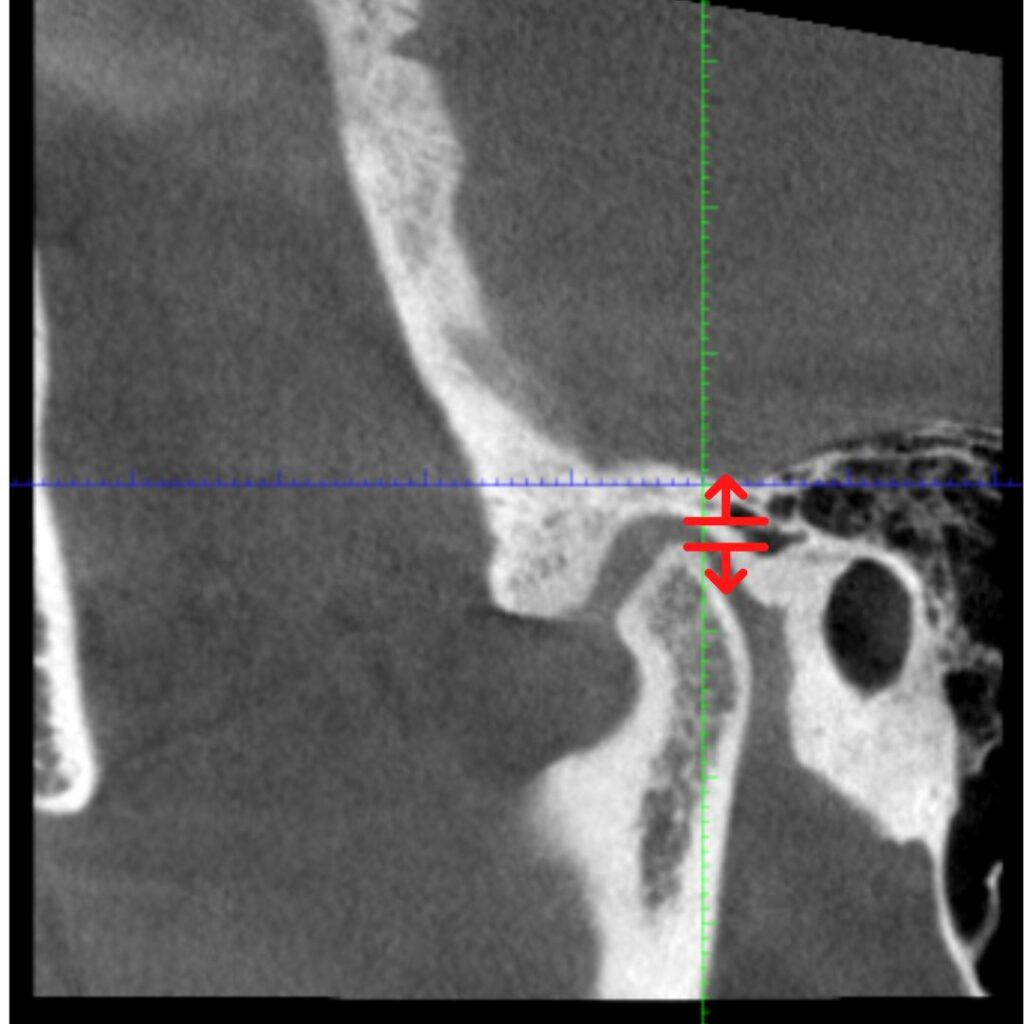

こちらはスタート時の顎の位置です。

こちらのエックス線ですが、こちらの赤い丸の部分となるのですが

食いしばりが激しそうな顎の位置になっています。

耳に顎関節の頭が近接してきていて、めまいや、耳鳴りなどを

引き起こすような位置です。

↑上下間スペースが狭く、全体に関節ごと後ろ上に行っています。

長年かかってくるってしまった噛み合わせによる顎の位置が

体の姿勢を狂わせ、頭痛などの不定愁訴を起こさせます。